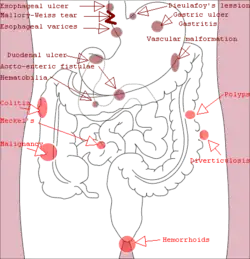

Bleeding is typically divided into two main types: upper gastrointestinal bleeding and lower gastrointestinal bleeding.[2] Causes of upper GI bleeds include: peptic ulcer disease, esophageal varices due to liver cirrhosis and cancer, among others.[3] Causes of lower GI bleeds include: hemorrhoids, cancer, and inflammatory bowel disease among others.[2][1] Small amounts of bleeding may be detected by fecal occult blood test.[1] Endoscopy of the lower and upper gastrointestinal tract may locate the area of bleeding.[1] Medical imaging may be useful in cases that are not clear.[1] Bleeding may also be diagnosed and treated during minimally invasive angiography procedures such as hemorrhoidal artery embolization.[10][11]

Gastrointestinal bleeding can be roughly divided into two clinical syndromes: upper gastrointestinal bleeding and lower gastrointestinal bleeding.[2] About 2/3 of all GI bleeds are from upper sources and 1/3 from lower sources.[14] Common causes of gastrointestinal bleeding include infections, cancers, vascular disorders, adverse effects of medications, and blood clotting disorders.[2] Obscure gastrointestinal bleeding (OGIB) is when a source is unclear following investigation.[15]

Upper gastrointestinal bleeding is from a source between the pharynx and the ligament of Treitz. An upper source is characterised by hematemesis (vomiting up blood) and melena (tarry stool containing altered blood). About half of cases are due to peptic ulcer disease (gastric or duodenal ulcers).[3] Esophageal inflammation and erosive disease are the next most common causes.[3] In those with liver cirrhosis, 50–60% of bleeding is due to esophageal varices.[3] Approximately half of those with peptic ulcers have an H. pylori infection.[3] Other causes include Mallory-Weiss tears, cancer, and angiodysplasia.[2]

Lower gastrointestinal bleeding is typically from the colon, rectum or anus.[2] Common causes of lower gastrointestinal bleeding include hemorrhoids, cancer, angiodysplasia, ulcerative colitis, Crohn's disease, and aortoenteric fistula.[2] It may be indicated by the passage of fresh red blood rectally, especially in the absence of bloody vomiting. Lower gastrointestinal bleeding could also lead to melena if the bleeding occurs in the small intestine or proximal colon.[1]